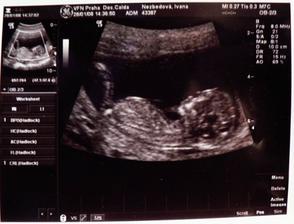

Taaak, otehotnela jsem na 3. pokus, vsechno probiha uplne normalne, ted (14tt) se uz citim docela dobre, nevolnost odchazi, ale hlavne vime, ze nase miminko je zdrave a nema zadne vyvojove vady. Takze si zacinam tehotenstvi naplno uzivat a hrozne moc se na miminko tesim 🙂